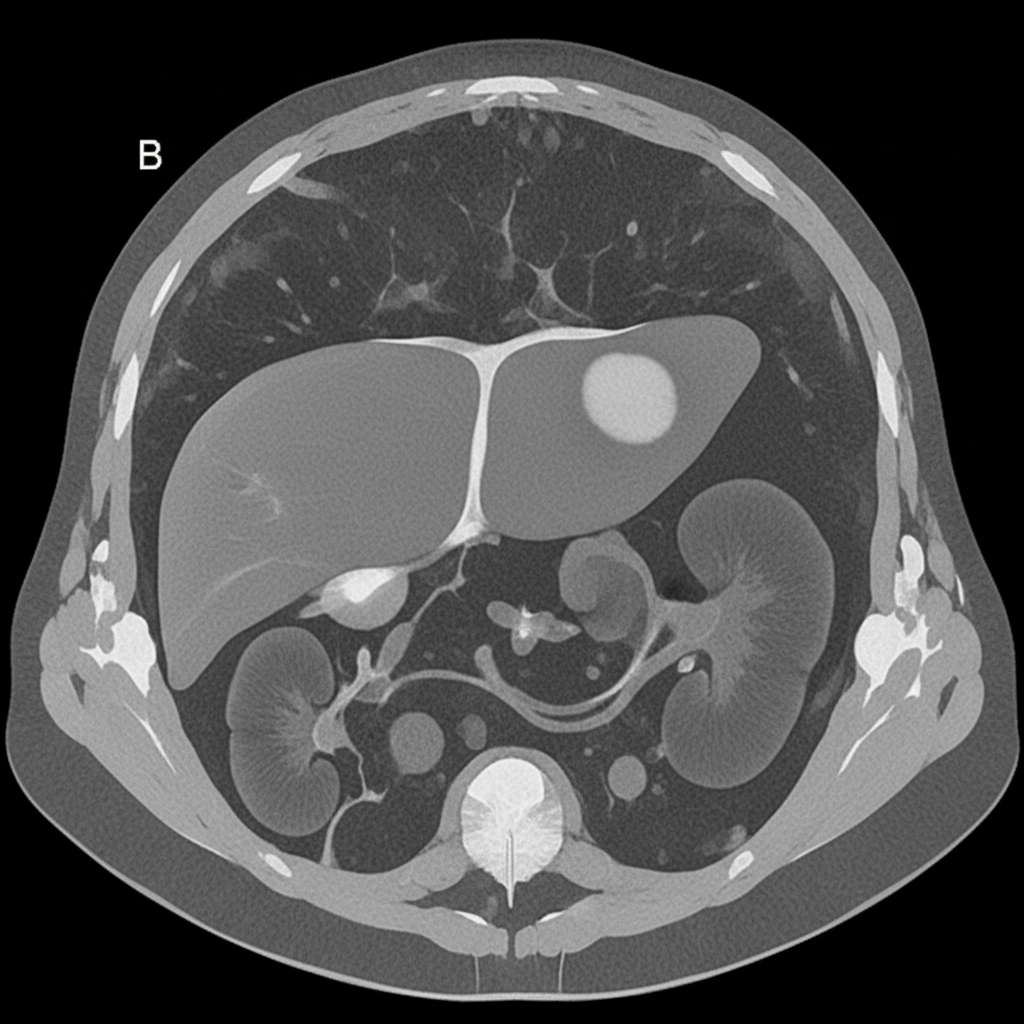

A 27-year-old woman presents with acute abdominal pain in her right upper quadrant. The pain came on suddenly while she was eating dinner. After this pain she began feeling dizzy and came to the emergency department. In the ED, her blood pressure is 75/40 mmHg, pulse is 100/minute, and she is afebrile. On physical exam, she feels too light-headed to ambulate. She demonstrates normal bowel sounds with tenderness upon palpation in the right upper quadrant. The patient is deemed too unstable for imaging. An abdominal radiograph and CT are reviewed from a recent previous visit to the ED for mild abdominal pain, and are shown in Figures A and B, respectively. Which of the following specific additional findings in her history supports the most likely diagnosis?